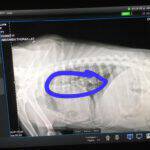

Natürlich wurde Luna gleich zur Erstuntersuchung zum Tierarzt gebracht. Gesundheitlich hatte diese süße Hündin ein bisschen Pech. So hatte sie nicht nur den Tumor, sondern auch die Tests auf Leishmaniose und Zeckenbissfieber fielen positiv aus. Selbstverständlich wird sie bei uns mit den passenden Medikamenten versorgt und steht unter genauer Beobachtung. Auch gab es eine Ultraschalluntersuchung um sicher zu gehen, dass sie keine weiteren Tumore hat. Die Wunde von der Tumorentfernung ist zum Glück schon fast verheilt.

Im November 2021 waren wir mit Luna wieder zum Check-up beim Tierarzt, weil sie verdächtige Knoten an der Brust/Lymphdrüsen hat. Leider hat die Untersuchung ergeben, dass der Krebs zurück ist und sich in den Lymphen und der Lunge ausgebreitet hat. Eine Operation wird wahrscheinlich nicht möglich sein. Luna geht es aber gut im Moment und wir tun alles, damit das auch so bleibt. Unsere größte Freude wäre, wenn unsere liebe Maus noch ihre eigene Familie finden würde!